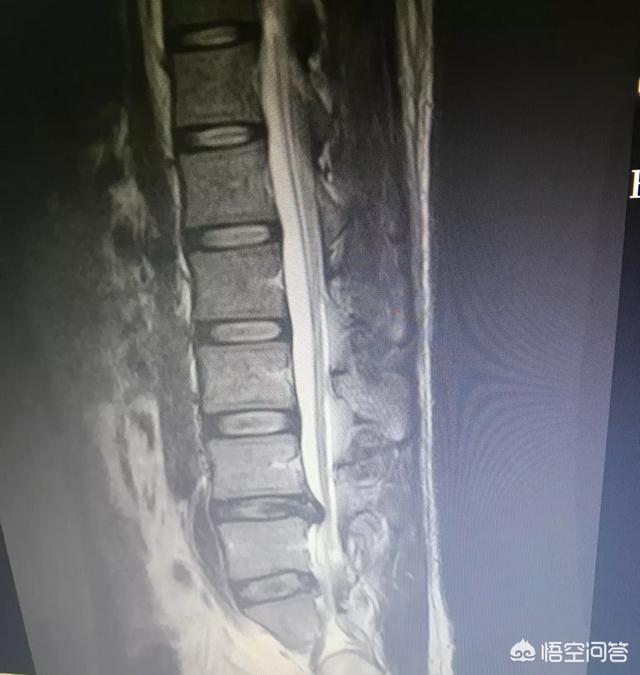

严不严重需要看突出的间盘,突出程度,突出部位。还有椎体后关节的稳定程度。如果在神经根发出的肩部、神经根出椎间孔的部位或者侧隐窝突出,神经根受压就很严重。如果不是上述部位,而且是腰五骶一这种神经根走行比较长的、椎体后关节稳定的,就不算严重,经过适当的非手术疗法可以稳定病情,免除手术。但是如果出现鞍区麻木就非常严重了,必须马上!立刻!手术!解除压迫。不然终身大小便都不受控制,更不说生殖功能了。